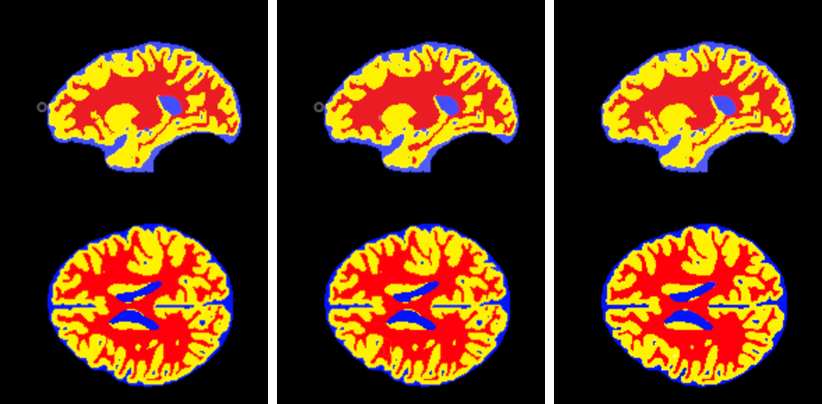

Refer to captionRefer to captionRefer to captionRefer to captionRefer to captionRefer to captionRefer to caption

Fig. 2: Qualitative iSeg sample results (from left to right: Ground-Truth, cscSE-UNet, and our MDA-Net. Blue: cerebrospinal fluid, yellow: gray matter, red: white matter.

Tables 1 and 2 report the segmentation results for iSeg and IBSR datasets, respectively. The brain segmentation performance for both datasets is steadily improved from plain U-Net, to cscSE-UNet, to MSE-UNet, and then to MDA-Net for each image view. The improvement of MSE-UNet over cscSE-UNet demonstrates the effectiveness of using MSE-Blocks in U-Net, and the improvement of MDA-Net over MSE-UNet demonstrates the effectiveness of using the slice-wise compression. Also, replacing Sigmoid with Softmax improves the stability and convergence of the network training. Figure 2 shows a qualitative comparison for the iSeg dataset.